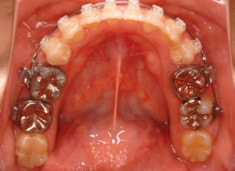

治療開始時